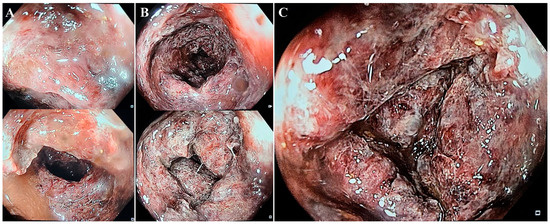

The histological report described focal superficial necrotic lesions in the colonic mucosa, covered by fibrin and hemorrhagic debris, and deep hemorrhagic lesions with cryptic destruction consistent with ischemic colitis due to infectious agents (Figure 4).

Rectoscopy or colonoscopy and tissue biopsies complete the investigational plan for achieving a positive diagnosis. In our case, although the entire colon was affected, the endoscope could reveal no further than 40–60 cm from the anal canal because of the risk of iatrogenic colon perforation. Histological biopsies from the colon or rectum may show similar patterns to those in ischemic colitis, such as atrophic crypts, coagulative necrosis of the mucosa, hyalinized lamina propria, and fibrin thrombi [6].

Figure 4. Histopathologic findings. Moderate to severe injury of the colonic mucosa, ranging from acute inflammation associated with focal superficial hemorrhagic lesions to lamina propria necrosis and cryptic damage with fibrinous exudate and vascular congestion, compatible with acute colitis. Hematoxylin-eosin; original magnification ×20 (A), ×10 (B) respectively.